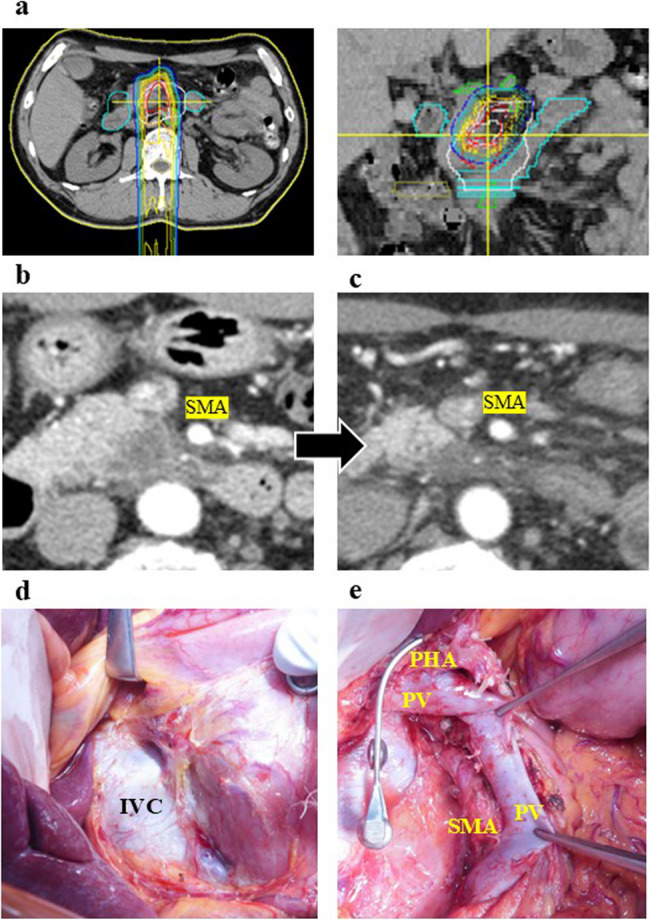

Methods: A retrospective single-center analysis was conducted on patients with locally advanced pancreatic cancer who underwent multidisciplinary treatment, including PBT, chemotherapy and hyperthermia (January 2014 to December 2022). PBT target dose was 67.5 Gy concurrently gemcitabine infusion and local hyperthermia was applied 1 h after gemcitabine infusion. The standard chemo regimens (such as gemcitabine with nab-paclitaxel or FOLFIRINOX) followed triple-modal treatment. Surgical complications, pathological assessment and survival were analyzed in resected cases.

Results: Among 133 patients treated with PBT, 110 underwent triple-modal treatment combining PBT, hyperthermia, and chemotherapy. Ultimately, 11 patients underwent tumor resection after a median preoperative treatment duration of 210 days. Surgical procedures included five pancreaticoduodenectomies and six distal pancreatectomies. Three patients experienced complications of Clavien-Dindo grade 3 or higher (2; delayed gastric empty, 1; pancreatic fistula), but no mortality occurred. Histological evaluations revealed three cases of Grade 4 (27%, pathological complete response), four of Grade 3, three of Grade 2, and one of Grade 1. R0 resection was achieved in 10 cases.